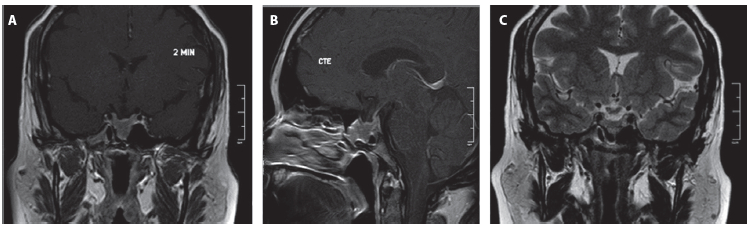

Paciente femenina de 37 años con historia de obesidad grado III, a quien por sintomatología inespecífica de mareos se le realizó una TC cerebral que encontró un hallazgo incidental de masa selar, corroborado por IRM de silla turca con evidencia de una lesión selar compatible con adenoma hipofisario (Figura 1). No tenía evidencia clínica de síntomas por déficit o exceso hormonal, la evaluación neuroftalmológica y los campos visuales fueron normales. El perfil hipofisario mostró como única alteración una leve elevación de la prolactina atribuida al efecto compresivo sobre el tallo hipofisario; se descartó efecto Hook con valores de prolactina diluida (Tabla 1).

Figura 1. Resonancia de hipófisis previa al inicio del tratamiento. A. Secuencia T1 contrastada, corte coronal. B. Secuencia T1 contrastada, corte sagital. C. Secuencia T2, corte coronal. Se identifica una masa cuyo diámetro era de 24 mm anteroposterior x 25 mm longitudinal x 21 mm transverso, con un volumen tumoral de 6,3 mL, en contacto con el quiasma óptico y con extensión al seno esfenoidal.